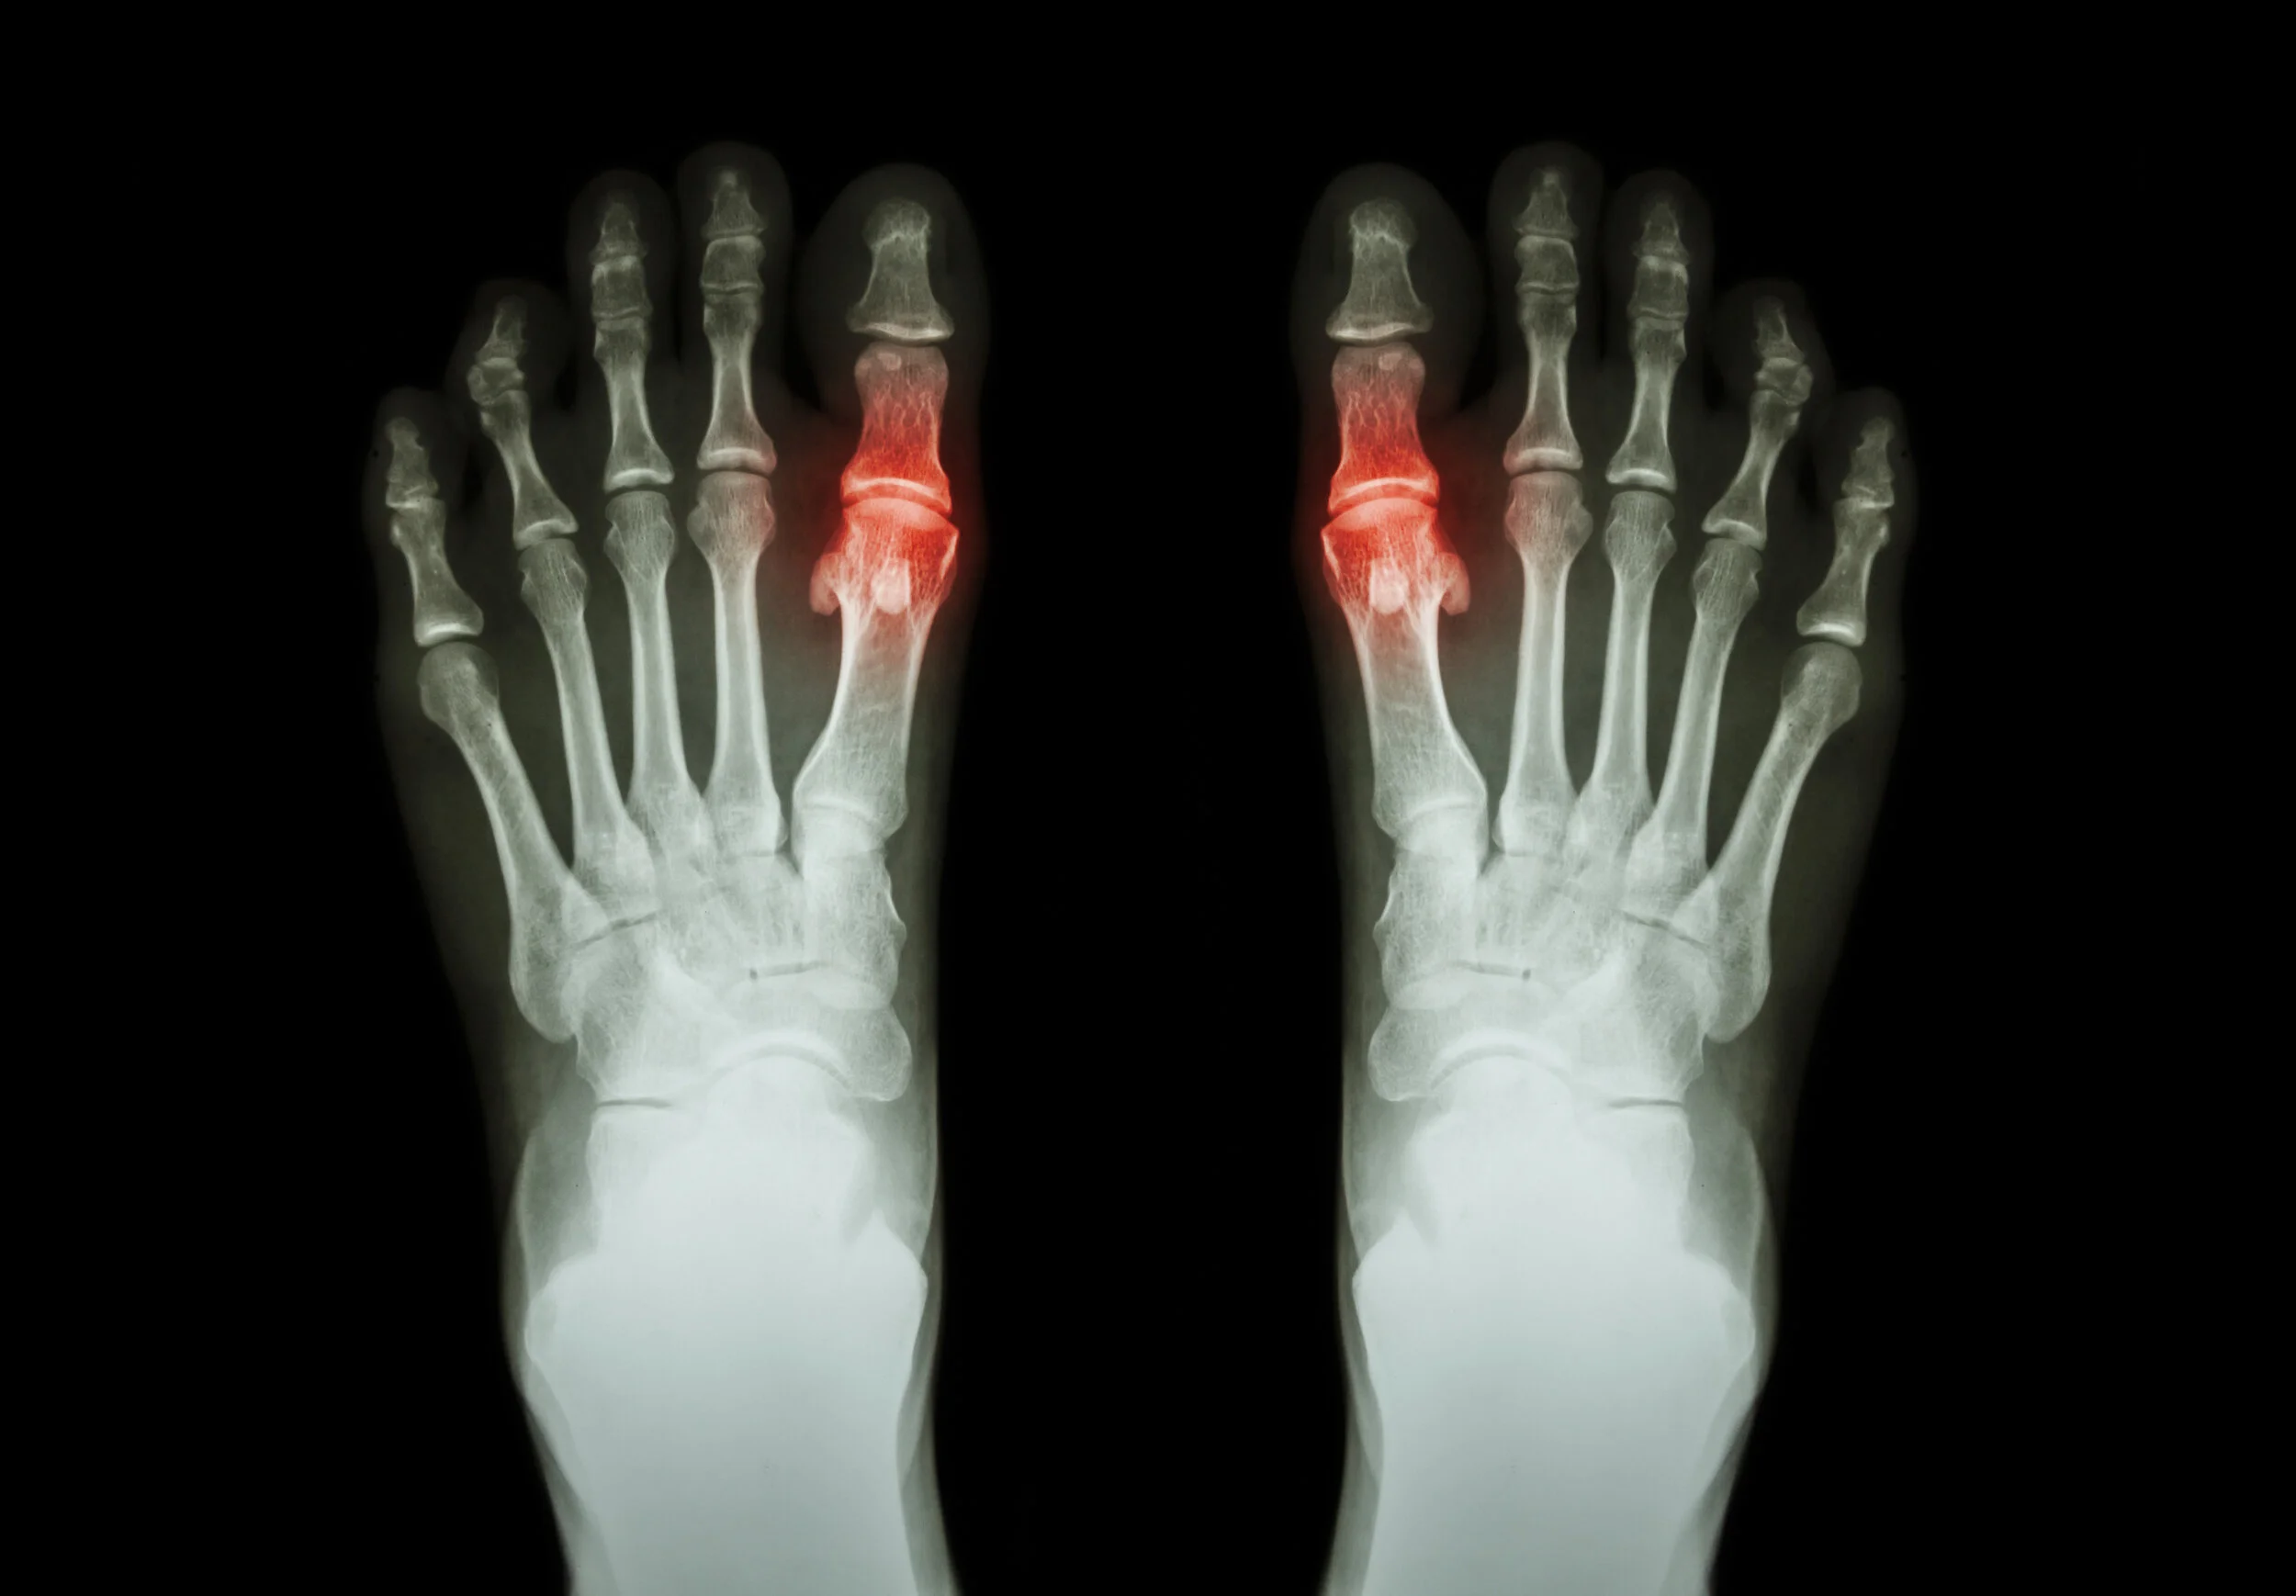

The plantar plate is a ligament that runs along the ball of your foot, connecting the toe joints. When strained, it can tear, causing pain and instability.